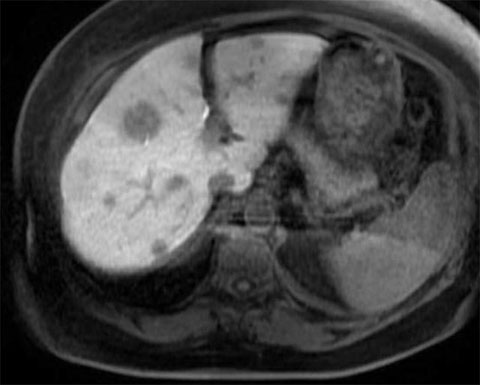

Pre-treatment MRIs

The patient responded well to chemotherapy; in a six-month period from December 2021 to May 2022, there was a significant interval decrease in the size of multiple hepatic metastatic lesions. The patient had approximately 22 peripherally enhancing liver metastases.

We identified 12 total lesions on the patient’s liver; five of these were in segment 2, one was in segment 1, four were in segment 3 and two were in segment 4A.